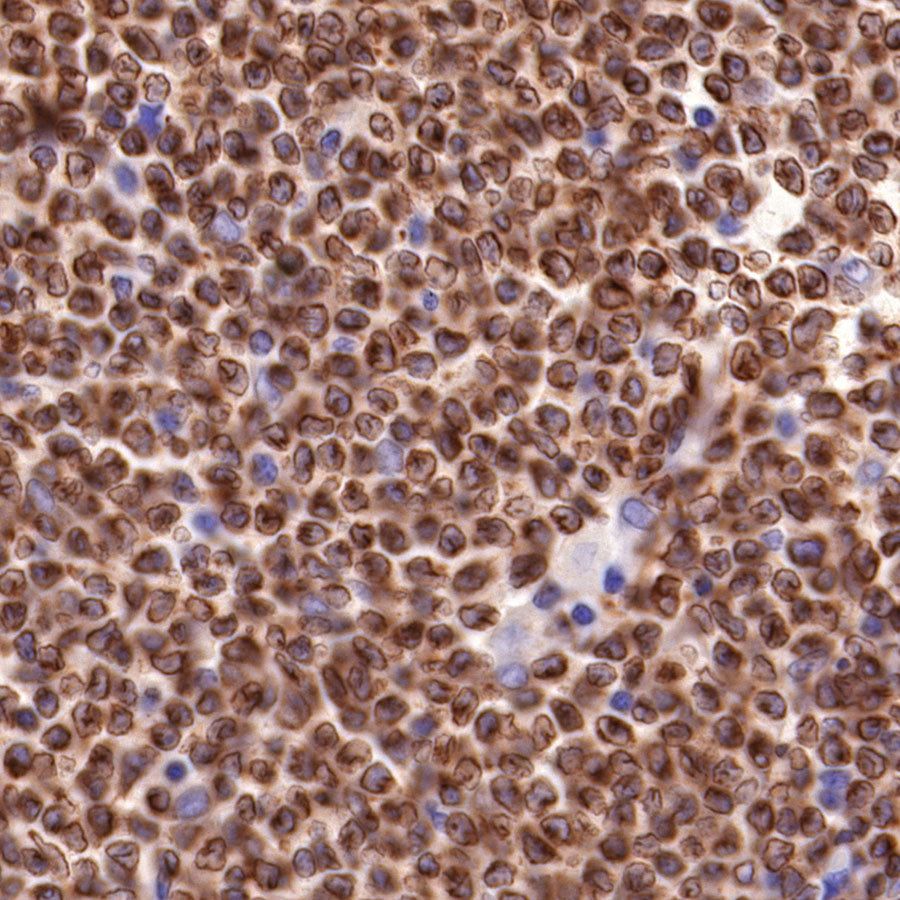

Picture

Picture

Immunohistochemistry